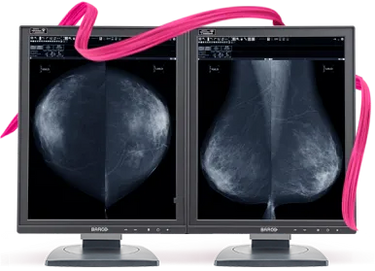

Barco Nio Fusion MDNC-12130 12MP 31" Color Tomosynthesis 3D-DBT Mammography Display

Barco Nio MDNC-6121 5MP 21" Color LED Mammo 3D-DBT Breast Imaging Display

Barco Nio MDNG-5221 5MP 21" Grayscale LED 3D-DBT Mammography Breast Imaging PACS Display

Barco Coronis MDMG-5221 5MP 21" Grayscale Tomosynthesis 3D-DBT Mammography Display

Barco Coronis UNITI MDMC-12133 12MP 33" Tomo Color LED Mammo 3D DBT PACS Display